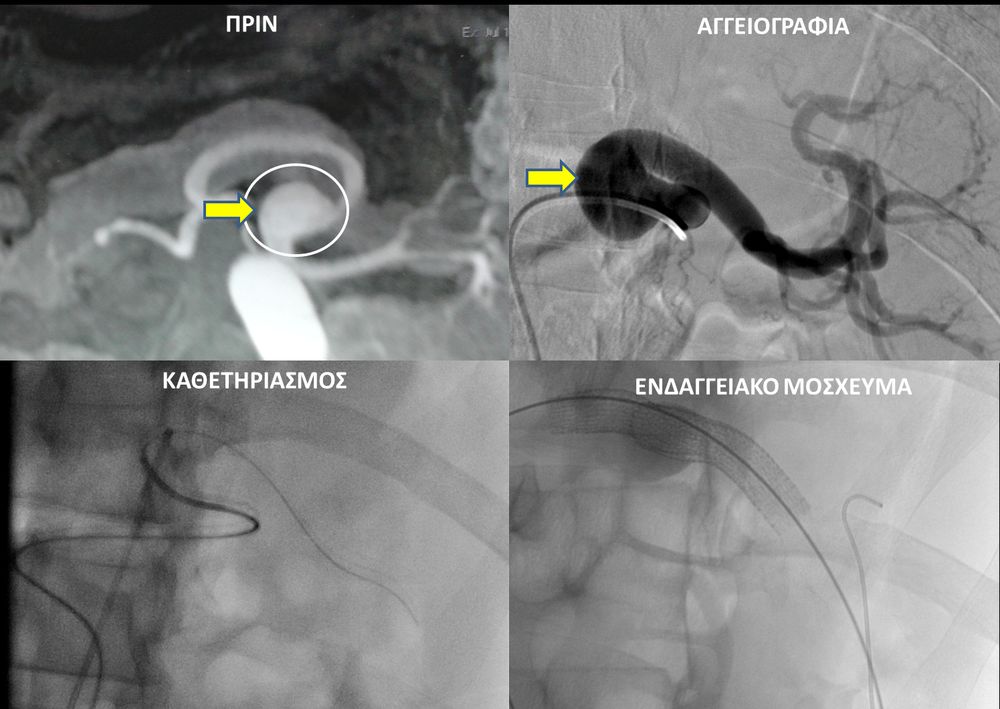

Ο επεμβατικός ακτινολόγος θα προσεγγίσει το παθολογικό αγγείο ενδοαυλικά και με απεικονιστική καθοδήγηση θα τοποθετήσει τακατάλληλα υλικά αποκατάστασης του ανευρύσματος. Υπάρχουν μια σειρά από επιλογές θεραπείας και η θεραπεία, που θα επιλεχθεί, εξαρτάται από την τοποθεσία και το σχήμα του ανευρύσματος.Μία πιθανή επιλογή για ενδαγγειακή θεραπεία περιφερικής αρτηρίας είναι η χρήση ενδαγγειακού μοσχεύματος stent-graft. Εναλλακτικά, το εσωτερικό του ανευρύσματος μπορεί να γεμίσει με εμβολικό υλικό (μικρά σπειράματα-coils ή ειδικη κόλλα), το οποίο εμποδίζει την ροή αίματος στο ανεύρυσμα.